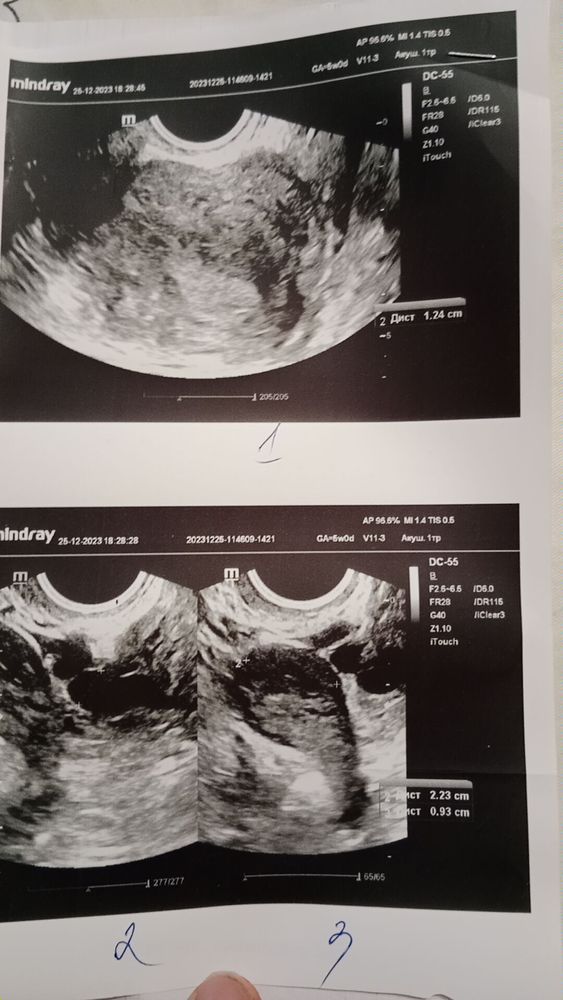

Забежала после работы на узи

Аня, сделала узи сегодня фото добавила

Аня, да сходила по месячным беременность 7 недель по Узи только 5, гинеколог сказала было две овуляции с разных сторон.

Dina, первая овуляция была справа но не оплодотворилась и там остатки желтого тела которое начало распадаться.

Слева была втора овуляция причем она была по срокам на 2 день задержки.